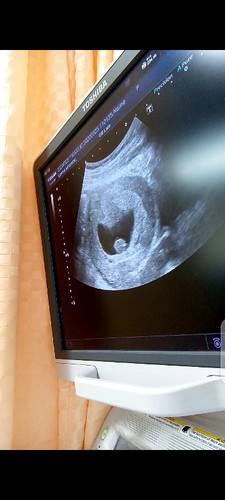

8w2d ท้องสองยังเห่ออยู่

เห็นตัวน้องแล้ว น้องมีหัวใจเต้นแล้วค่ะ ตอนนี้สบายใจขึ้นเยอะเลยค่ะ ไม่ต้องกังวลว่าจะเป็นท้องลมอีกต่อไป ทีแรกที่เห็นคือดีใจมากๆเลยค่ะ นี่ขนาดท้องสองนะคะ